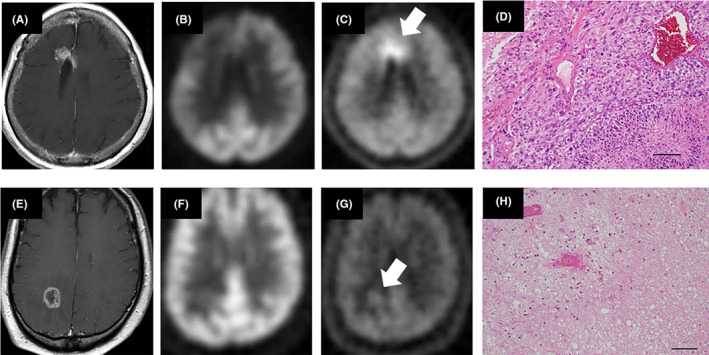

FIGURE 3.

Typical cases of tumor recurrence (A‐D) and radiation‐induced necrosis (E‐H) in the surgical group. Contrast‐enhanced T1‐weighted magnetic resonance images (A, E), 18F‐fluorodeoxyglucose (FDG) positron emission tomography (PET) images (B, F), 11C‐methionine (MET) PET images (C, G). In both cases, the affected lesions did not show an uptake of 18F‐FDG but an uptake of 11C‐MET was detected (arrows). Histopathological findings of each of the lesions demonstrated tumor recurrence with viable tumor cells (D) and radiation‐induced necrosis without viable tumor cells (H), respectively

The flowchart and breakdown of eligible patients are shown in Figure 2. Two patients could not undergo surgery because of rapidly decreasing clinical status. Among the 39 patients who underwent surgery, one patient was excluded from the final evaluation due to a violation of protocol—namely, that the biopsy site was not recorded during the surgical procedure. Thus, 56 cases, 38 surgical and 18 observation cases, were assigned as acceptable for inclusion. Among the 38 surgical cases, viable tumor cells were detected in the specimens from targeted lesions in 32 cases (84%), whereas viable tumor cells were not detected in six cases (16%). Representative cases are shown in Figure 3. In the 18 observation cases, only one case (6%) had an increase in the size of the target lesion. This patient underwent resection of the lesion, and tumor recurrence was confirmed histopathologically. In the remaining 17 cases (94%), the size of the target lesion was confirmed to be stable or to have decreased. These lesions were definitively diagnosed as radiation‐induced necrosis.